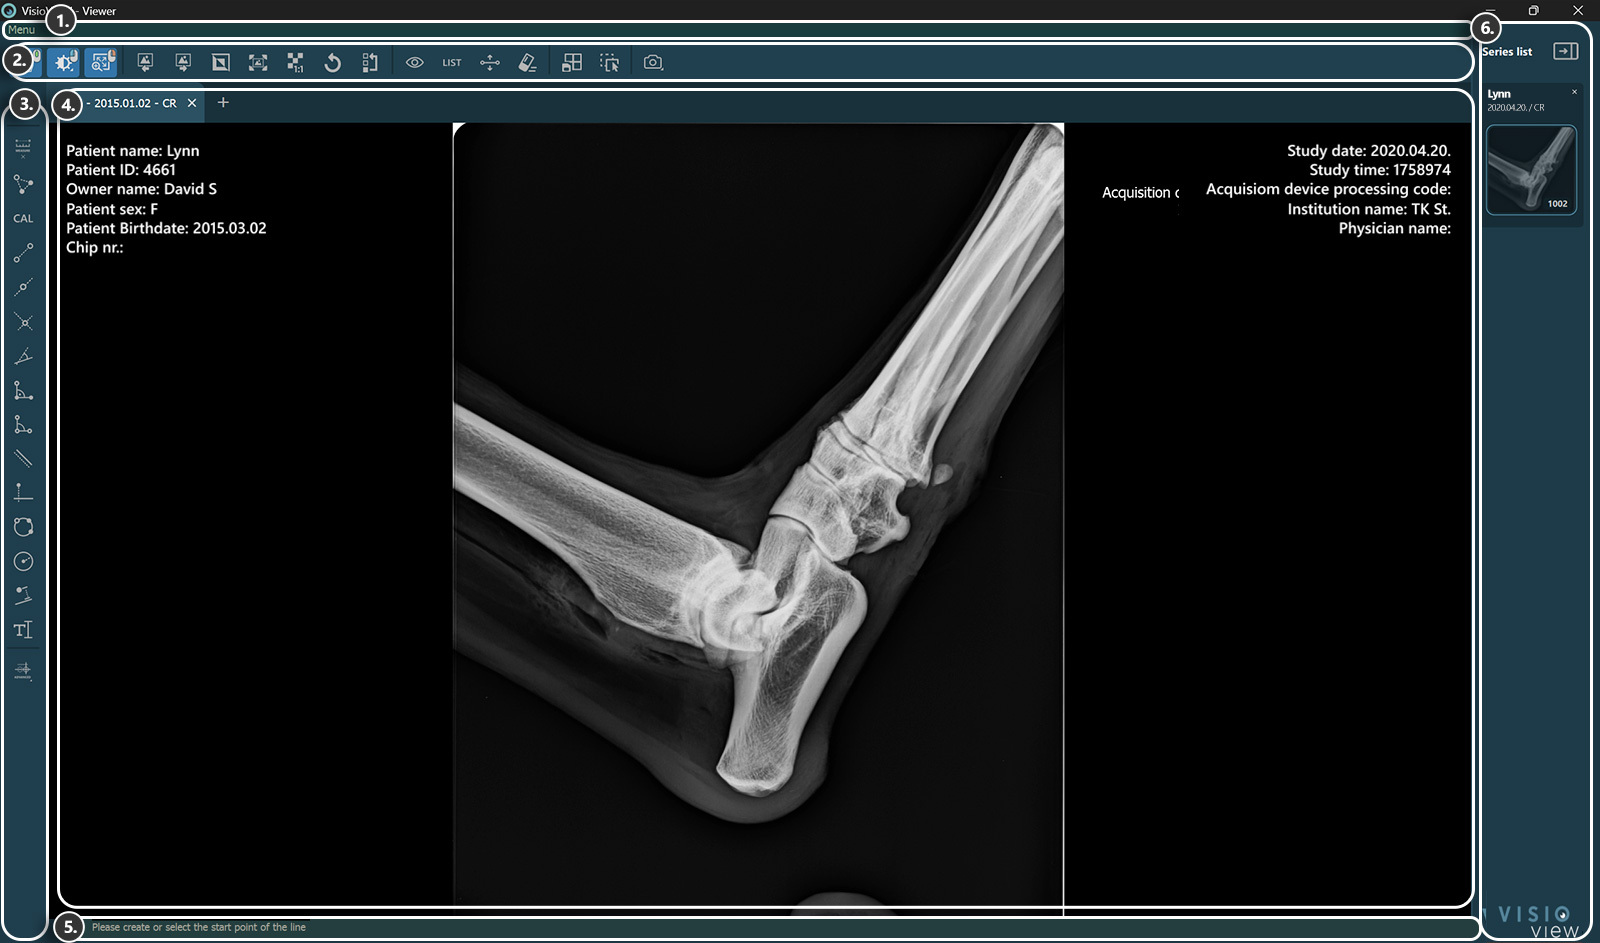

VisioVIEW - Megjelenítő¶

A VisioVIEW Megjelenítő szakaszai¶

A VisioVIEW Megjelenítő több szakaszból áll, amelyek mindegyike egy adott célnak felel meg. Az alábbiakban az egyes szakaszok részletes leírása található.

Megjelenítő felület¶

Beteginformáció

Tanulmányi információk

Információs sáv¶

Információkat vagy utasításokat jelenít meg az aktuálisan kiválasztott eszközről.